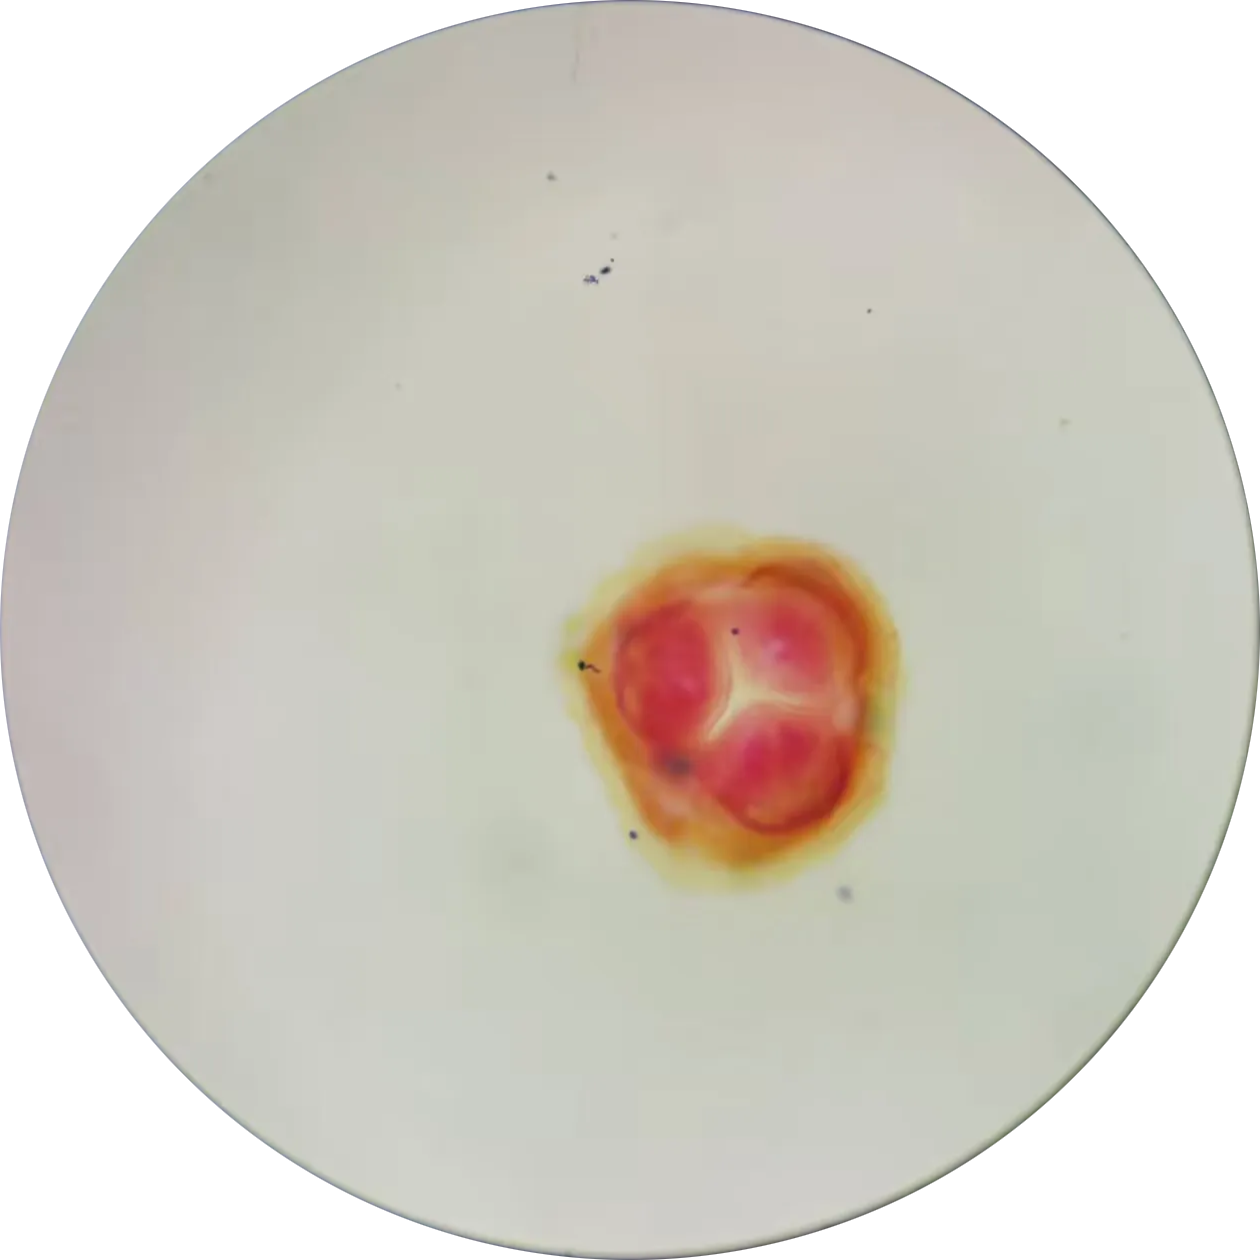

蛔虫唇瓣